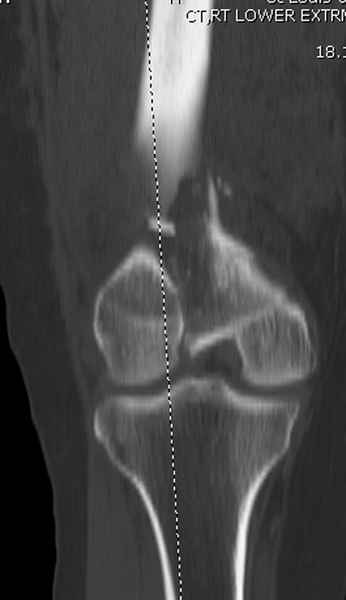

Приветствую всех коллег!!Во первых слева хотелось бы видеть четкую боковую проекцию а лучше КТ. По р-мам есть сомнения насчет повреждения суставной поверхности. При подобных переломах даже внутрисуставных без смещения хорошие результаты показал закрытый ретроградный остеосинтез универсальным бедренным стержнем Деост.Кстати при внутрисуставном переломе возможно применение вместо винтов стягивающих болтов!!(См. метод.Деост).При переломе справа также стержень Деост. Однако без открытия Вам не удастся устранить интерпозицию, только промучаетесь!Из минимального разреза удалите интерпозициб и фиксируйте стержнем. Причем универсальный стежень Деост позволяет фиксировать дистально минимум на трех уровнях!